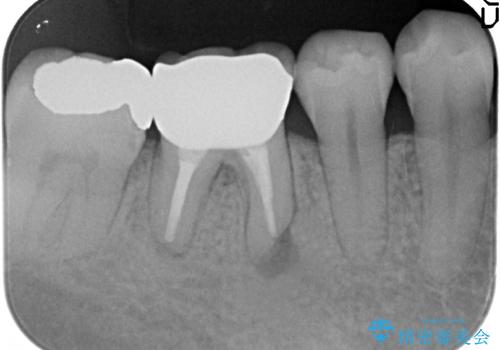

オールセラミッククラウン 膿が出続ける根の治療

- 数年前から歯茎から膿が出る、治療してもよくならないので診て欲しいといらっしゃった方の症例です。

再根管治療を行い膿の出口の消失及び根尖病変の縮小を確認後、オールセラミッククラウンによる補綴を行いました。